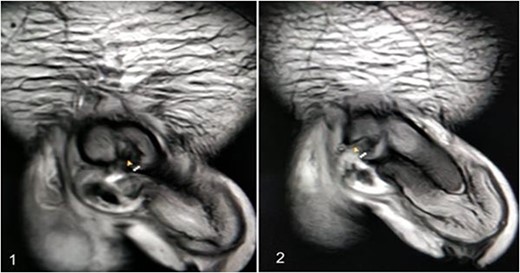

A 37-year-old male presented with a history of a ‘snap’ sound and immediate detumescence of penis during intercourse, when he fell and hit the pubic bone of his partner. There was generalized swelling and pain in the penis. There was acute retention of urine, an attempt to pass a catheter failed and the patient underwent supra-pubic catheterization. On examination, there was classical ‘eggplant deformity’ of the penis with blood at the tip of the meatus. MRI showed a tunical tear on both sides at the penoscrotal junction with indistinct urethra and extensive hematoma in the proximal penile shaft (Fig. 1). With the diagnosis of a fractured penis and possible urethral injury, after proper counselling, the patient was taken up for surgery. On the table, a retrograde urethrogram (RGU) was done showing evidence of partial urethral disruption. On exploration with penoscrotal vertical incision, there was total transection of proximal penile urethra, and a 1.5 cm tunical injury of corpus cavernosum on both sides ventrally (Fig. 2). There was extensive hematoma. Corpora sutured with 4.0 prolene after reconstructing the midline septum. Urethral ends mobilized and anastomosed with 3.0 vicryl in a single layer with minimal spatulation (Fig. 3). The patient was discharged on the 5th post-operative day; Foley catheter was removed on day 21. Follow-up RGU done after 3 months showed no evidence of stricture (Fig. 4).

An MRI with (1) left corporeal tear on the left side with surrounding hematoma and (2) right corporeal tear with hematoma and disruption of urethra.